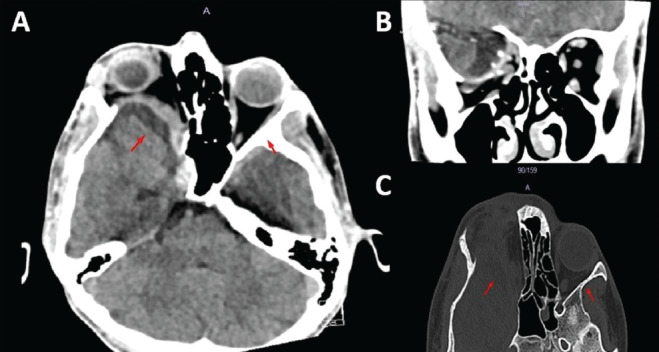

In this study, we aimed to present a rare case of pulsatile proptosis due to sphenoid wing dysplasia without the features of neurofibromatosis type 1 (NF1). A 17-year-old male patient presented with swelling in the superotemporal region of the right eye. Physical examination revealed facial asymmetry with a pulsatile, ill-defined, soft lesion with in the superotemporal region of the right orbit associated with pulsatile proptosis, downward dystopia, and hypotropia. Computer tomography imaging to establish a differential diagnosis showed temporal lobe herniation secondary to sphenoid wing dysplasia. The patient was assessed for NF1, which is most commonly associated with sphenoid wing dysplasia, but no evidence supporting the diagnosis was found. Patients presenting with proptosis should be carefully examined for pulsation and murmurs, and a trauma history should be investigated. Radiological imaging should be used to facilitate the differential diagnosis, and the current clinical condition should be managed with a multidisciplinary approach.